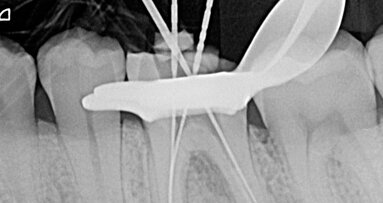

L’utilizzo della lega Ni-Ti (nichel-titanio) ha rappresentato un punto di svolta nella storia dell’odontoiatria; ha permesso, infatti, anche la ...